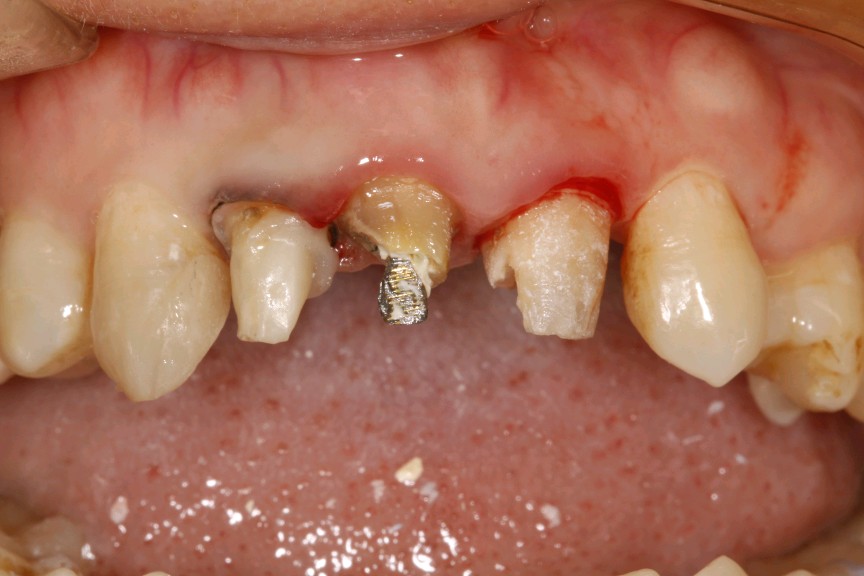

患者女,三十岁,11、12、21牙已行根管治疗,11、21烤瓷全冠修复。由于长时间烤瓷牙的佩戴,导致牙龈边缘发黑,颈缘处牙龈组织出现"黑线"。腭侧部分也出现了崩瓷的现象。对于这种情况,建议患者尽早重新修复,避免二次伤害。患者最终选择重新修复,也给出患者合理的方案,患者选全瓷冠修复,与今日佩戴完毕。边缘密合度良好,形态色泽自然美观,患者满意。

术中